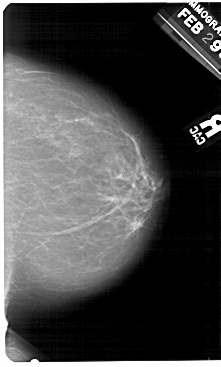

A_1493_1.RIGHT_CC

RIGHT_CC LINES 5491 PIXELS_PER_LINE 3301 BITS_PER_PIXEL 12 RESOLUTION 43.5 NON_OVERLAY